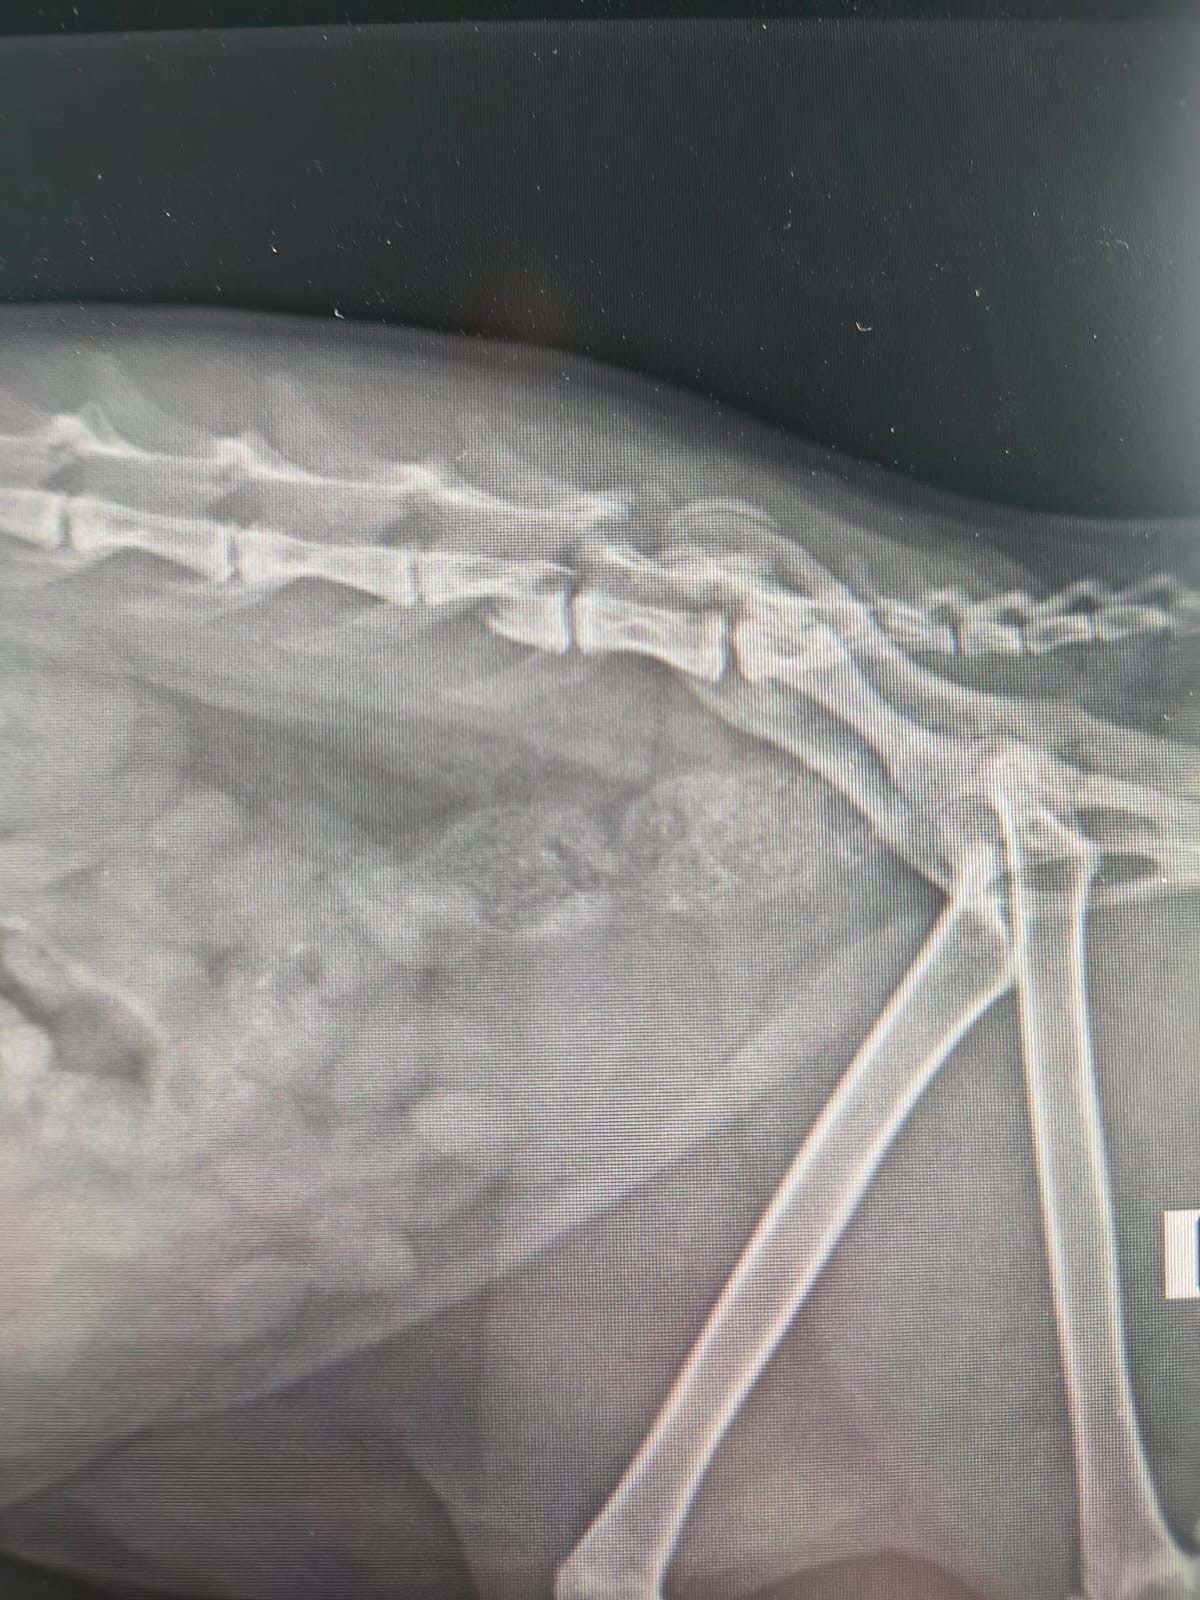

Ha una gravissima lesione alla colonna vertebrale, tra la quinta e la sesta vertebra.

- Esami specialistici (TAC, lastre, visite)